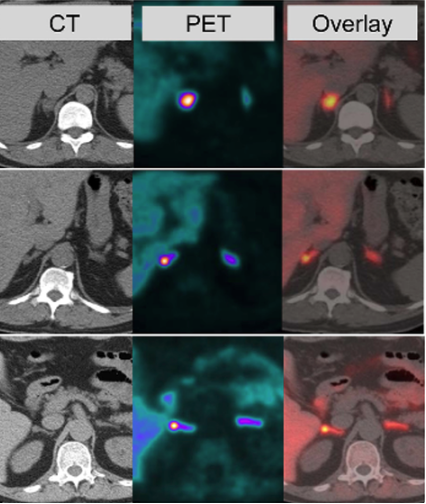

- Urine or plasma catecholamine excess - MRI scanning - MIBG scanning (Meta-iodobenzylguanidine) - Biochemistry - PET scanning - Gallium-Dotate scan

On which body region would MRI scanning be performed in phaeochromocytoma?

MRI scanning is usually performed on the abdomen or pelvis, unless a paraganglioma is suspected, in which a whole body scan is performed